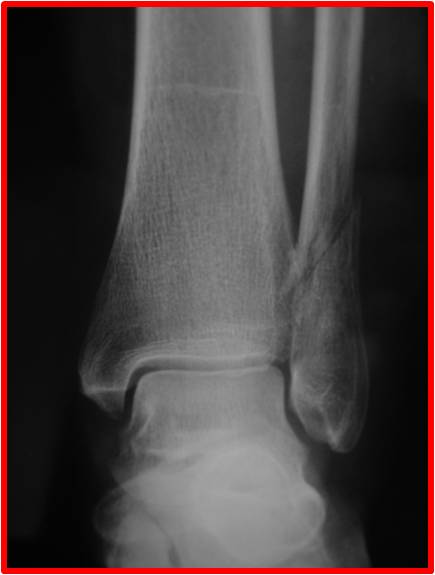

Fractures de la cheville

Fracture malléole externe